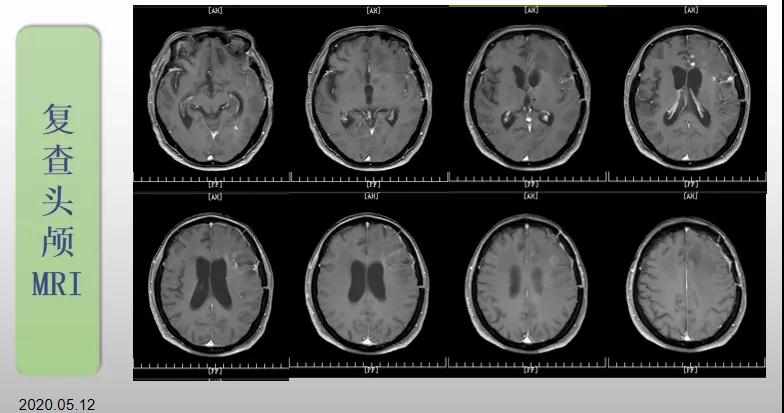

綜合治療 電場治療助70歲患者回歸正常生活

70歲的郝女士去年曾在外院查出“左額島葉”膠質(zhì)母細(xì)胞瘤(WHO Ⅳ級(jí)),并做了左側(cè)額島葉占位性病變切除術(shù)。術(shù)后進(jìn)行了同步放化療。由于治療條件有限,郝女士慕名來到我院就診。賀世明主任率領(lǐng)醫(yī)護(hù)團(tuán)隊(duì)立即為郝女士進(jìn)行了全面的檢查,決定為其進(jìn)行綜合治療 電場治療。經(jīng)過三個(gè)多月的綜合治療,患者復(fù)查頭顱MRI病變較前明顯縮小。出院時(shí),郝女士神志清醒,睡眠飲食正常,說話很流利?!拔沂翘芍M(jìn)來的,現(xiàn)在不用人攙扶,自己就可以走出病房了。”郝女士拉著醫(yī)護(hù)人員的手說。